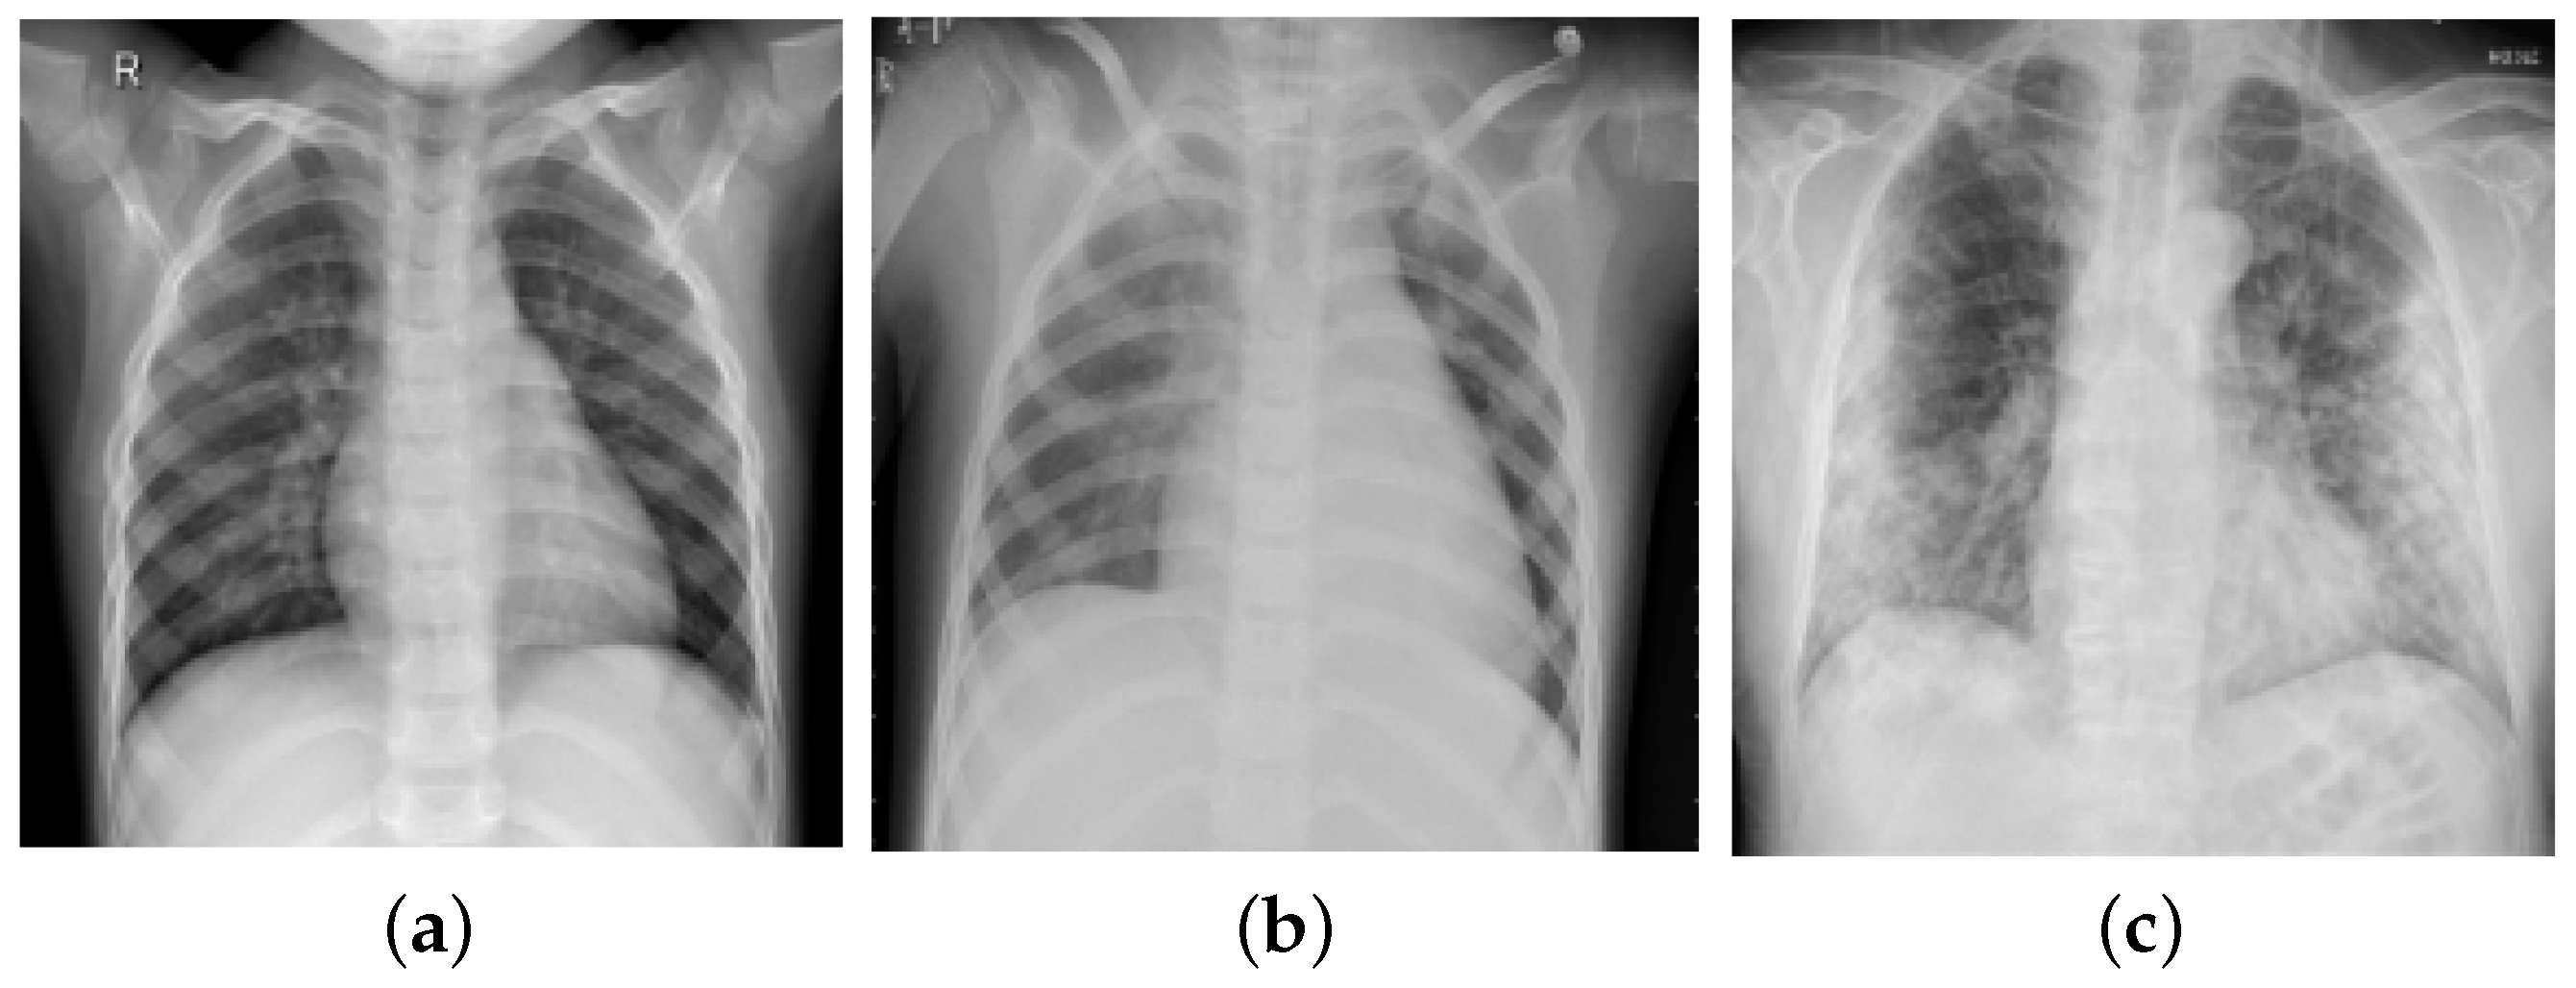

Healthcare Free FullText Detection of COVID19 Patients from CT Scan and Chest Xray Data Covid Detection Using Chest X Ray the main purpose of this work is to investigate and compare several deep learning enhanced techniques applied to x. Covid Detection Using Chest X Ray.

Deep Learning to Identify COVID19 in Chest Xrays Johns Hopkins Malone Center for Engineering Covid Detection Using Chest X Ray the main purpose of this work is to investigate and compare several deep learning enhanced techniques applied to x. Covid Detection Using Chest X Ray.

Diagnostics Free FullText An Efficient Deep Learning Method for Detection of COVID19 Covid Detection Using Chest X Ray the main purpose of this work is to investigate and compare several deep learning enhanced techniques applied to x. Covid Detection Using Chest X Ray.

Applied Sciences Free FullText An Effective Convolutional Neural Network Model for the Covid Detection Using Chest X Ray the main purpose of this work is to investigate and compare several deep learning enhanced techniques applied to x. Covid Detection Using Chest X Ray.